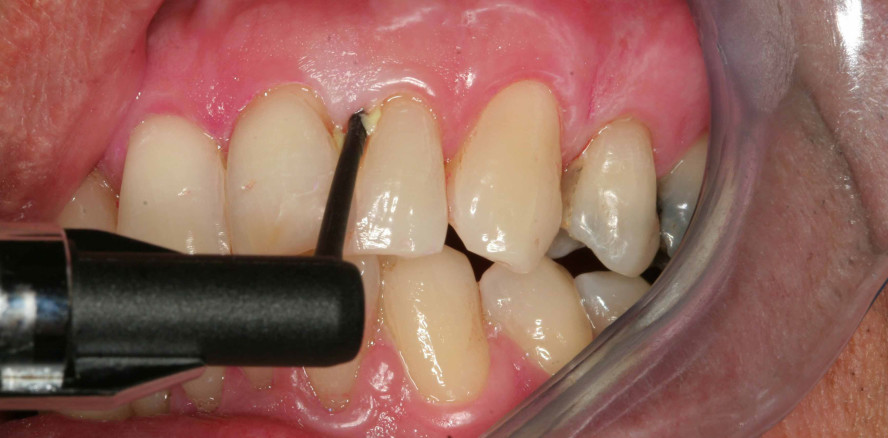

Ligosan® Slow Release, das innovative Lokalantibiotikum in Gelform von Kulzer, ergänzt die konventionelle, nicht-chirurgische Standardtherapie chronischer und aggressiver Parodontitis mit überzeugender Wirkung. Die Anwendung des Gels ist einfach und schnell.

Bei erwachsenen Parodontitispatienten mit Taschentiefen ab fünf Millimetern unterstützt Ligosan Slow Release (Wirkstoff 14%iges Doxycyclin) die Therapie effizient mit einer antibakteriellen als auch antiinflammatorischen Wirkung1: In den Studien konnte nachgewiesen werden, dass das Arzneimittel die Taschentiefen nach sechs Monaten stärker reduziert als durch alleiniges Scaling and Root Planing (SRP). Auch ist ein höherer Attachmenlevel-Gewinn zu verzeichnen.2 Weiterhin wurden die Studienergebnisse durch eine breit angelegte Anwendungsbeobachtung im niedergelassenen Bereich bestätigt.3

So gelingt die Anwendung von Ligosan Slow Release ganz unkompliziert